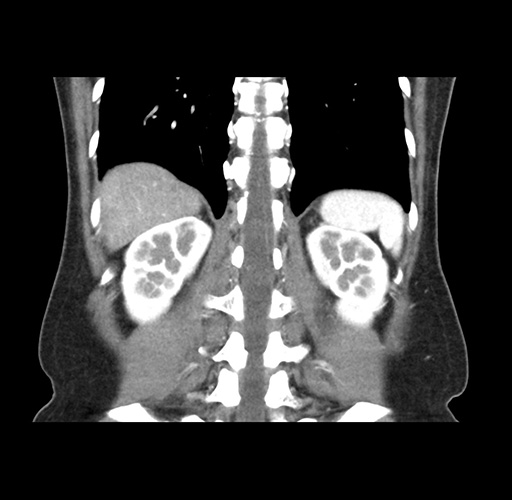

Imaging Analysis

Look through the patient's CT scan to identify any areas of concern for the necessary procedure.

Based on your CT findings, which issue(s) would give reason for "planned slowing down moment(s)" in this case?

Considering a standard left lateral sectionectomy procedure, what step(s) of the operation would you do differently in this case ?